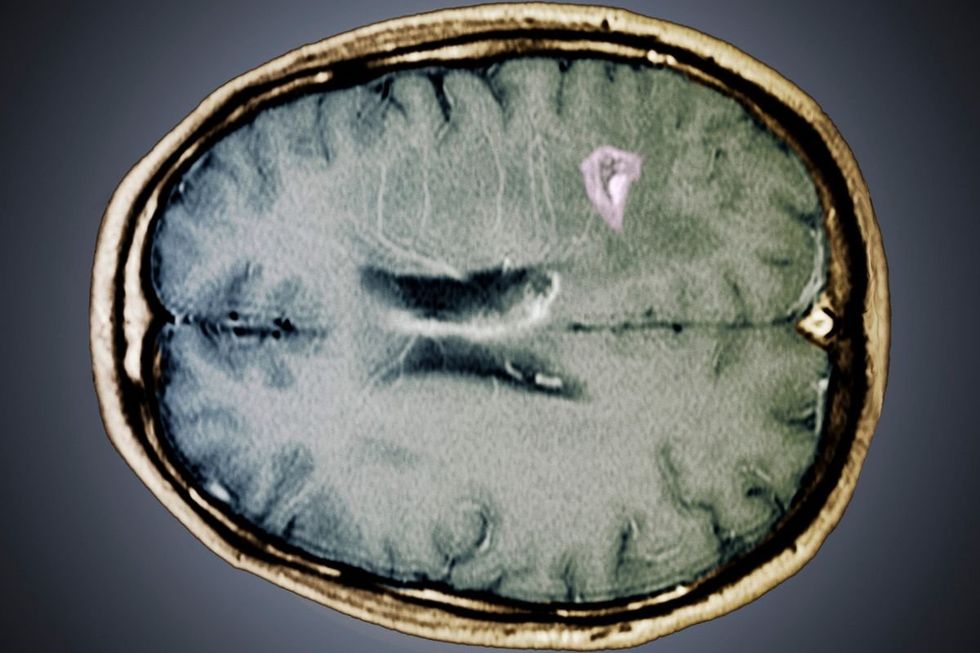

Strokes have many causes, but most are linked to long-term cardiovascular risk factors such as high blood pressure and other underlying vascular conditions. Three seemingly harmless habits may also have a link to the deadly condition, however.

Although the triggers will not pose a threat to most individuals, the physician explained they can occasionally set off a dangerous sequence of events culminating in stroke.

His advice centres on protecting the delicate blood vessels that supply oxygen to the brain. The first habit Dr Chen warns against is using massage guns on the neck area.

This region contains the carotid arteries along the sides and vertebral arteries at the rear, both essential for delivering oxygenated blood to the brain.

Forceful, rapid pressure applied to this sensitive zone can harm the arterial lining, potentially causing a dissection - a small tear within the vessel wall.

Should a tear occur, the body responds by forming a clot, which may dislodge and travel to the brain, triggering a stroke.